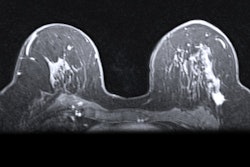

Representative MR images of ipsilateral (A) and contralateral (B) axillary lymph nodes modified in both size and shape before and after chemotherapy for a complete responder and nonresponder. Shape images are magnified to more easily see margins. Images courtesy of ISMRM.Using the I-SPY1 dataset, the researchers also sought to determine if they could predict an outcome before, during, and after chemotherapy based on tumor volume and shape independently. They found that sensitivities ranged from 38% to 76%, and specificities varied from 36% to 89% along the three time points.

Neoadjuvant chemotherapy also affected the shape of the axillary lymph nodes among responders. While the axillary lymph node started out with the same shapely characteristics, over the course of the treatment, normal nodes and responder nodes expressed similar distribution. Nonresponder nodes, however, maintained irregular shapes.

As one might expect, MR images showed a statistically significant reduction in the volume of ipsilateral nodes among patients who responded to neoadjuvant chemotherapy. Prior to treatment, the mean size of ipsilateral nodes was 2.33 (± 4.56) mL, compared with 0.45 (± 0.37) mL after therapy (p < 0.001).

Most interestingly, the volume of ipsilateral nodes also decreased significantly after treatment among patients who did not respond well to therapy. The mean volume was 2.58 (± 3.29) mL before treatment, compared with 0.77 (± 0.83) mL after neoadjuvant chemotherapy (p < 0.00001).